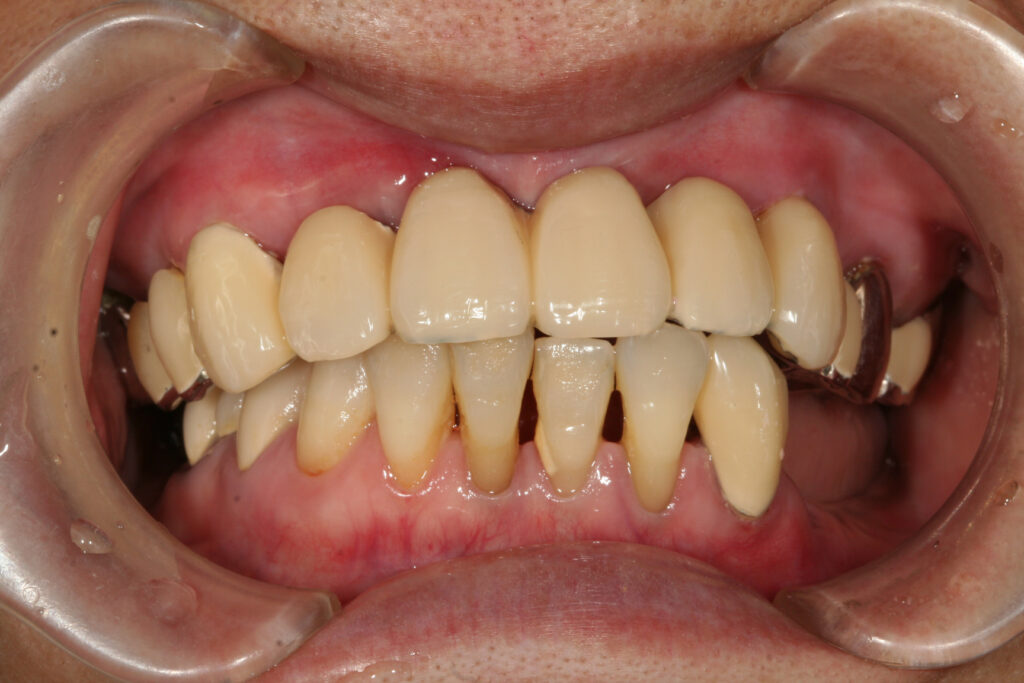

60代 女性 の方です。 一年前から前歯がグラグラしていて、何軒か歯医者に行かれたのですが、どこに行っても抜いて入れ歯にしかできないと言われていたそうです。

どうしても取り外しの入れ歯をしたくないと思われ、当クリニックを受診されました。

抜いたその日に仮の歯を取り付け、最終的には差し歯にしました。

治療回数は3回でした。